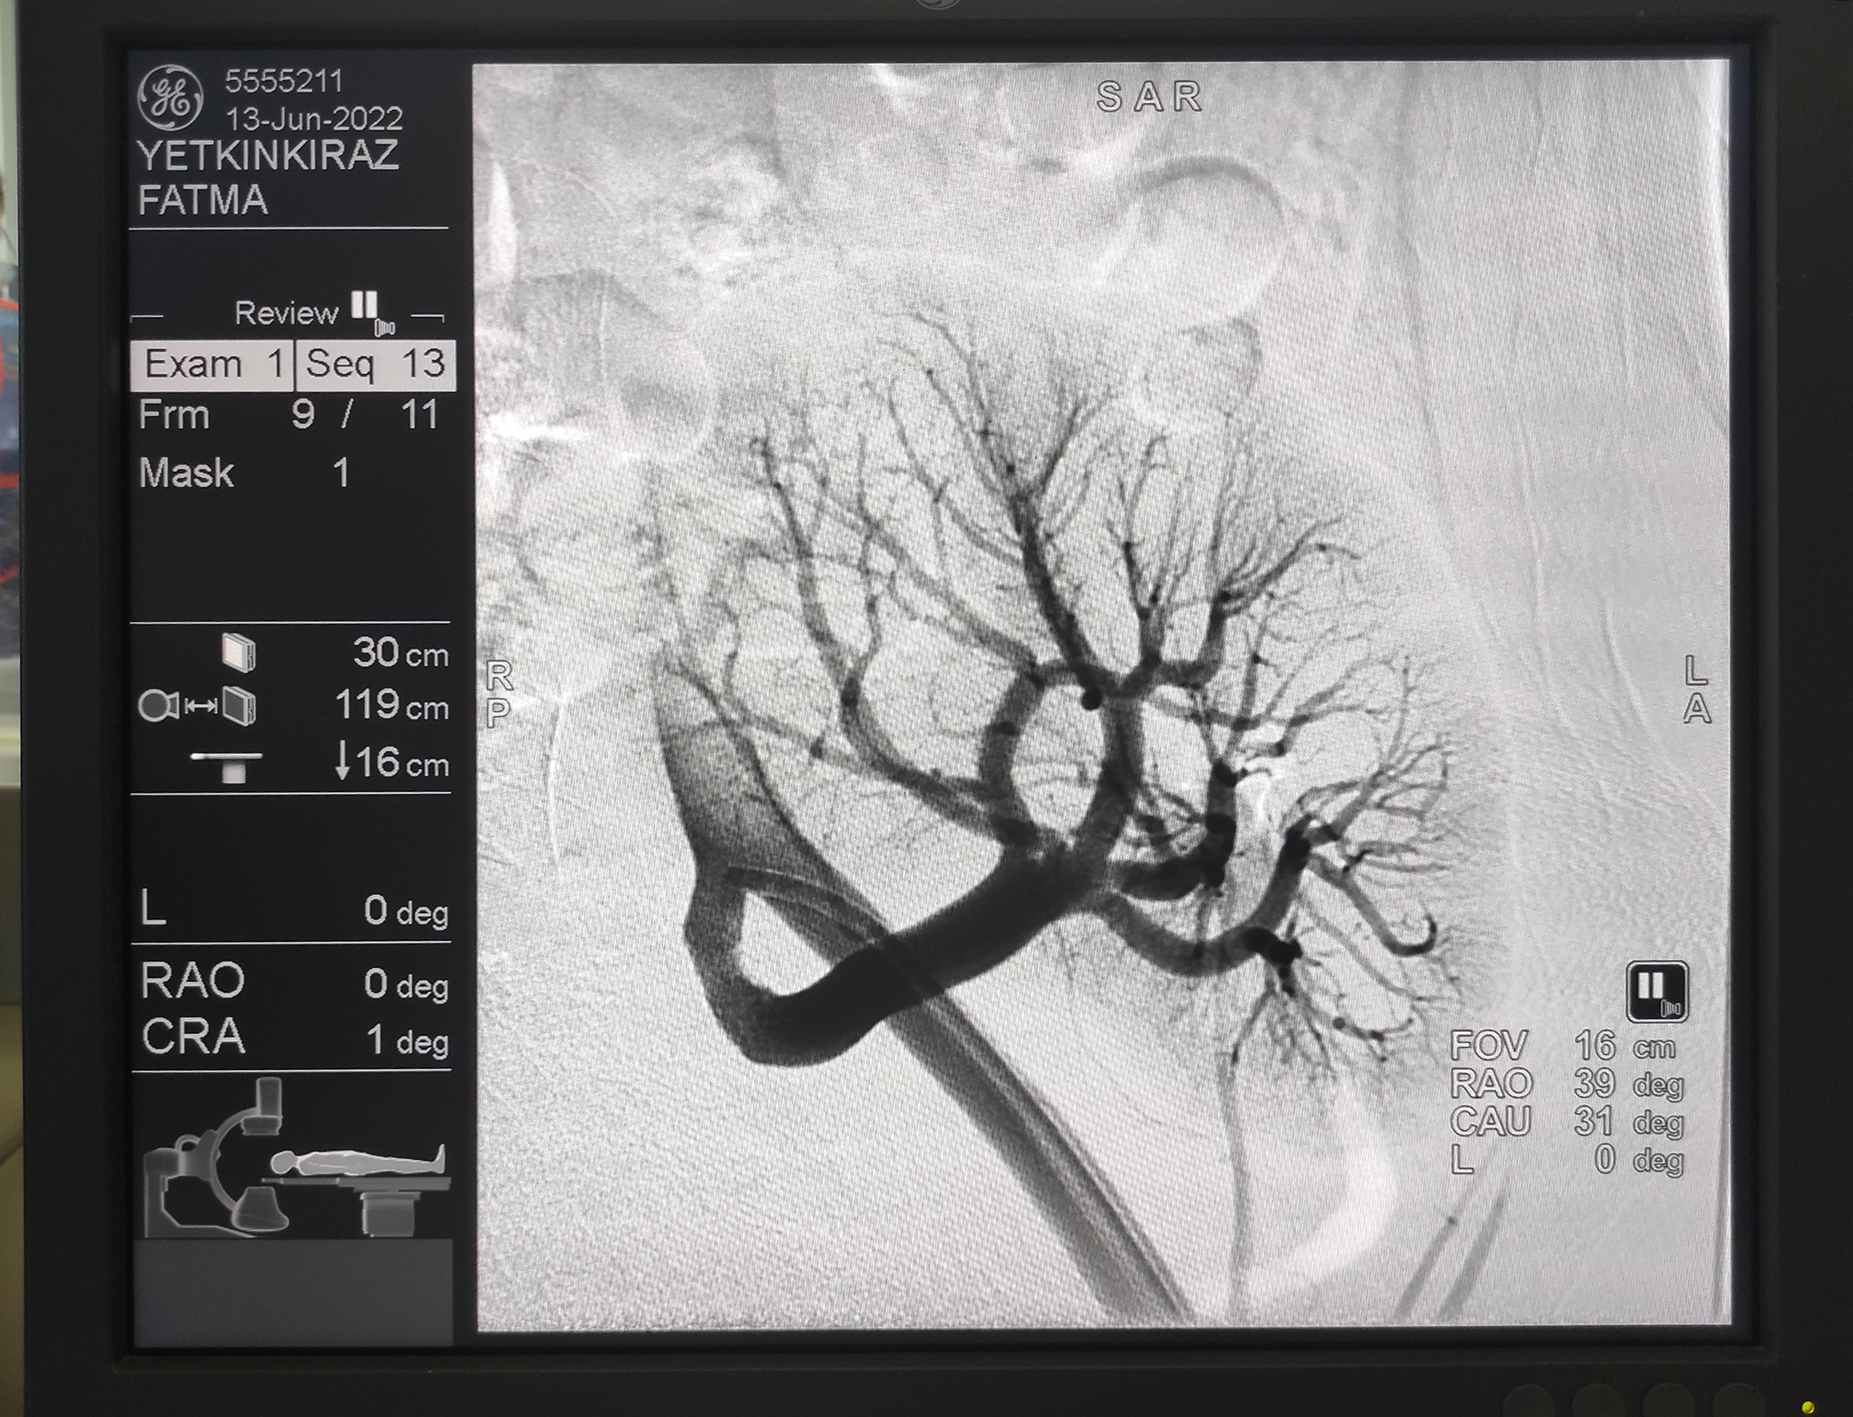

Kahramanmaraş Sütçü İmam Üniversitesi (KSÜ) Sağlık Uygulama ve Araştırma Hastanesi (Tıp Fakültesi Hastanesi) Kardiyoloji Anabilim Dalı Öğretim Üyesi Prof. Dr. Ahmet Çağrı Aykan, kardiyoloji kliniğinde anjiyo yöntemiyle yüzde 99 böbrek damarı tıkalı genç bir hastayı balon ve stent uygulaması yöntemiyle sağlığına kavuşturdu.

Konu hakkında açıklama yapan KSÜ Tıp Fakültesi Kardiyoloji Anabilim Dalı Öğretim Üyesi Prof. Dr. Ahmet Çağrı Aykan, “Hastamıza 2 yıl önce böbrek nakli yapılıyor. Nakil sonrası böbreğinin çalışmasıyla ilgili olarak hastada bir kusur gelişiyor. Hastanın böbrek kanalında yüzde 99’luk bir darlık oluşmuş. Bu yüzde 99’luk darlığa bağlı olarak böbrek, işlev yapma özelliğini kaybetmiş vaziyetteydi. Anjiyoda, hastanın nakil böbreğine darlığı gidermek için stent takarak böbrek damarını açtık. Böbrek damarını açmayla birlikte hastanın nakil böbreği kurtulmuş oldu. Nakil böbrek zaten az bulunan bir organ. Hastanın nakil böbreğini kurtararak, hastanın sağlıklı bir şekilde yaşamına devam etmesini sağlamış olduk. Bu işlemler bölgede yapılmayan işlemler. Civar illerden de hastaların bu tür hastalıkları olduğunda Kahramanmaraş Sütçü İmam Üniversitesi Kardiyoloji Bölümü’ne gelmekteler. Tedavilerini burada gerçekleştirip, sağlıklarına kavuşturmaktayız. Nakil böbreğe bu tarz işlem yapmak oldukça riskli ve ciddi tecrübe gerektiriyor. Civarda da bu tür işlemlerin yapıldığı söylenemez. Biz enstitümüzde kardiyoloji kliniği olarak bu işlemleri sıklıkla yapıyoruz. Civar ilçelere ve bölgeye sıklıkla hizmet eden kurum görevindeyiz.” şeklinde konuştu.